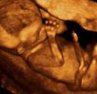

A négy dimenziós felvételek optimális időpontja a 22-30. terhességi hét,

de ettől eltérő időpontban is van rá lehetőség.

A 4 dimenziós felvételekkel családi eseménnyé emeljük a várandósok gondozását.